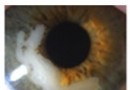

普通眼科资讯[临床精要][组图]青光眼滤过泡moorfields分级佚名01-05